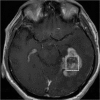

Purpose: To elucidate differences between glioblastoma (GBM) and primary central nervous system lymphoma (PCNSL) with MR image-based texture features.

Methods: This was an Institutional Review Board (IRB)-approved retrospective study. Consecutive, pathologically proven, initially treated 44 patients with GBM and 16 patients with PCNSL were enrolled. We calculated a total of 67 image texture features on the largest contrast-enhancing lesion in each patient on post-contrast T1-weighted images. Texture analyses included first-order features (histogram) and second-order features calculated with gray level co-occurrence matrix, gray level run length matrix (GLRLM), gray level size zone matrix, and multiple gray level size zone matrix. All texture features were measured by two neuroradiologists independently and the intraclass correlation coefficients were calculated. Reproducible features with the intraclass correlation coefficients of greater than 0.7 were used for hierarchical clustering between the cases and the features along with unpaired t statistics-based comparisons under the control of false discovery rate (FDR) < 0.05. Principal component analysis (PCA) was performed to find the predominant features in evaluating the differences between GBM and PCNSL.

Results: Twenty-one out of the 67 features satisfied the acceptable intraclass correlation coefficient and the FDR constraints. PCA suggested first-order entropy, median, GLRLM-based run length non-uniformity, and run percentage as the distinguished features. Compared with PCNSL, run percentage and median were significantly lower, and entropy and run length non-uniformity were significantly higher in GBM.

Conclusions: Among MR image-based textures, first-order entropy, median, GLRLM-based run length non-uniformity, and run percentage are considered to enhance differences between GBM and PCNSL.